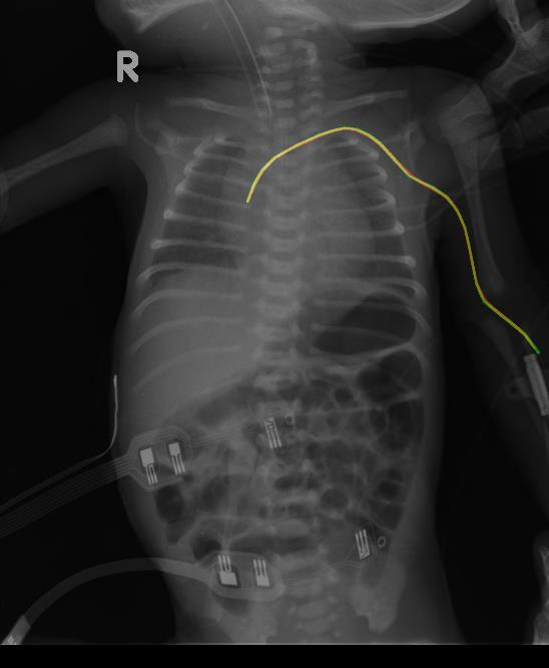

- 모델 출력: 영상과 동일한 크기의 카테터 영역이 표시된 이진 마스크 이미지로, 그 예시는 아래와 같음 (빨간색: 모델 예측 영역, 초록색: 정답 영역, 노란색: 모델이 정답을 맞춘 영역)

NG-tube 분할 결과